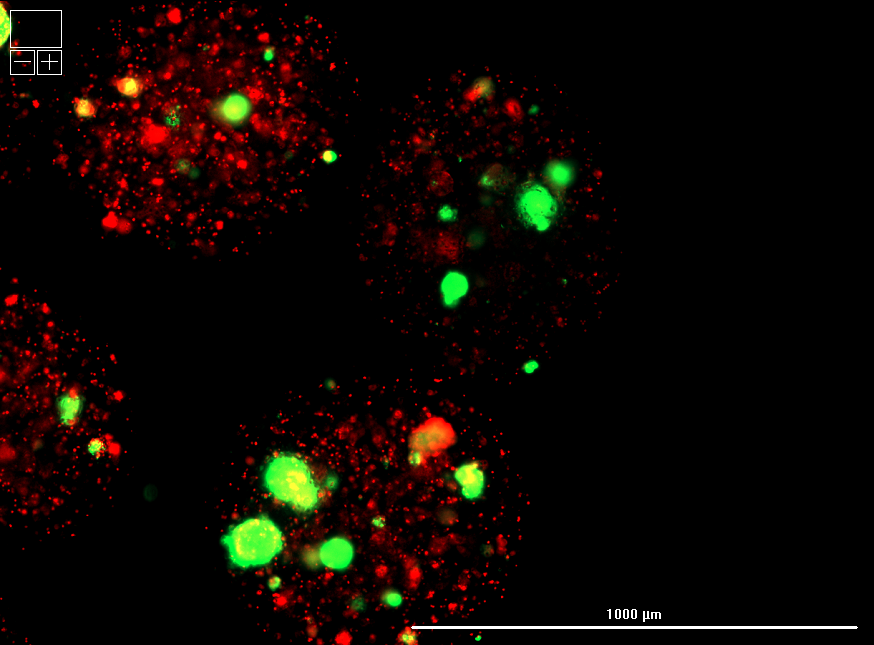

Encapsulated islets retained high viability and cellular integrity compared to standard (unencapsulated) cryopreservation, as confirmed by live/dead imaging.

Hydrogel polymer formulation #2 yielded superior survival and uniform morphology relative to formulation #1, highlighting tunability of the LiberaCell™ system.